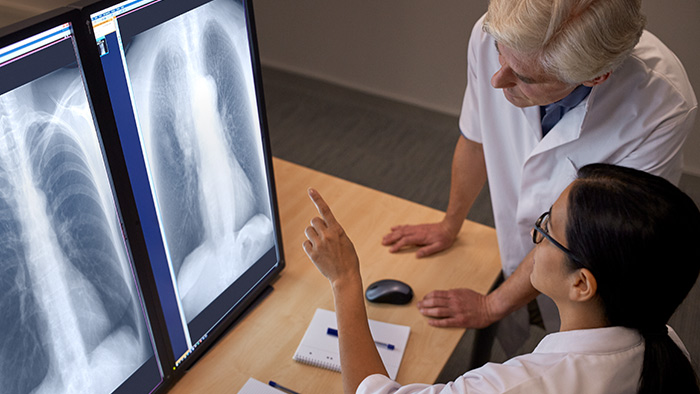

Bone Suppression2

Philips Bone Suppression2 is an innovative image enhancement technology. As an advanced, proven AI application it increases the clarity of adult erect chest radiographs by suppressing bones on digital images without the need for two exposures. This solution is integrated into the latest DigitalDiagnost C90 and CombiDiagnost R90 providing a soft tissue image for digital chest radiographs.